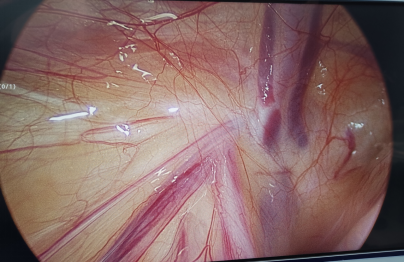

腸系膜淋巴結(jié)炎在兒童不少見,前陣子腹腔鏡手術(shù)探查同時發(fā)現(xiàn)腸系膜淋巴結(jié)明顯腫大,3-4厘米。平時超聲見到為主,但不是真實肉眼所見,今展示真實圖片一張。 腸系膜淋巴結(jié)炎表現(xiàn)為腹痛、發(fā)熱、消化道癥狀,易與其他外科急腹癥混淆。 急性腸系膜淋巴結(jié)炎多見于7歲以下小兒,好發(fā)于冬春季節(jié)。常繼發(fā)于上感或腸道炎癥。有腹痛、發(fā)熱、惡心、嘔吐,腹瀉或便秘。病變常累及回腸末端的一組淋巴結(jié),故腹痛發(fā)生于臍周或右下腹,查體往往腹部平軟,無固定壓痛點,無反跳痛及腹肌緊張。無全身中毒癥狀,白細胞輕度升高。應(yīng)與急性闌尾炎鑒別,無需手術(shù),保守治療后病情緩解可治愈